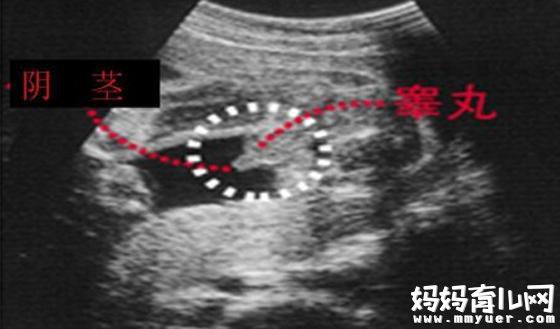

如果是彩超中有"凸出的东西" (如下图): 你们看到圆圆的是DANDAN,如果看到圆圆的加小肠的就是全部JJ